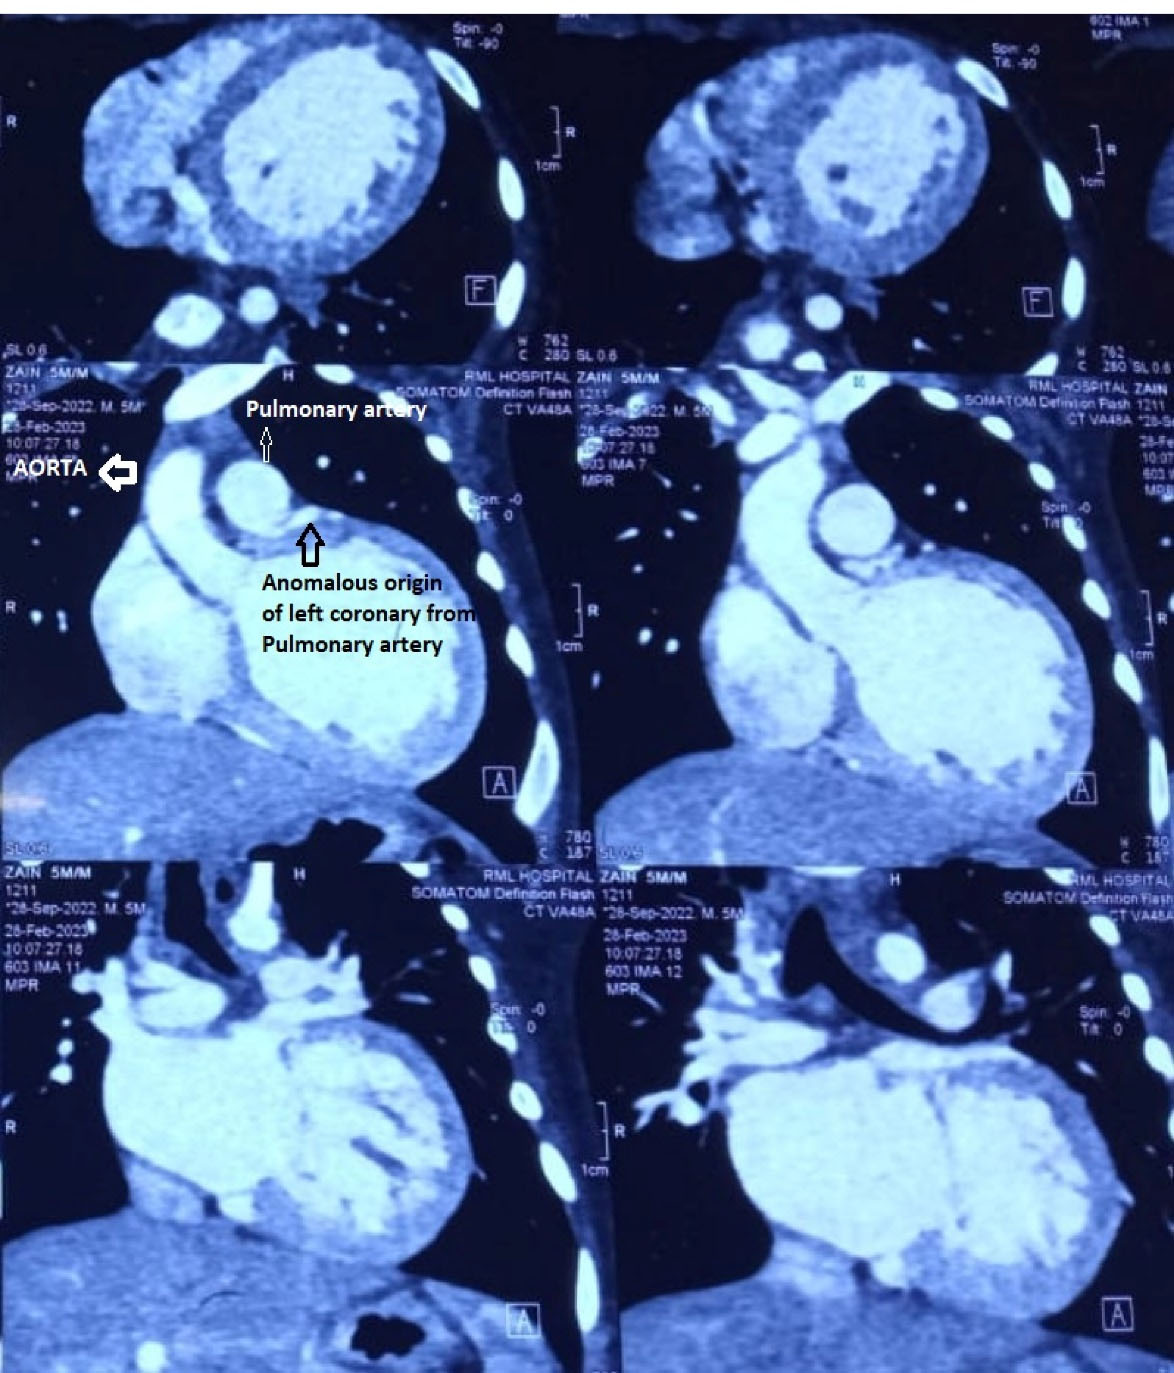

Figure 1.

CT angiogram showing anomalous origin of coronary from pulmonary artery